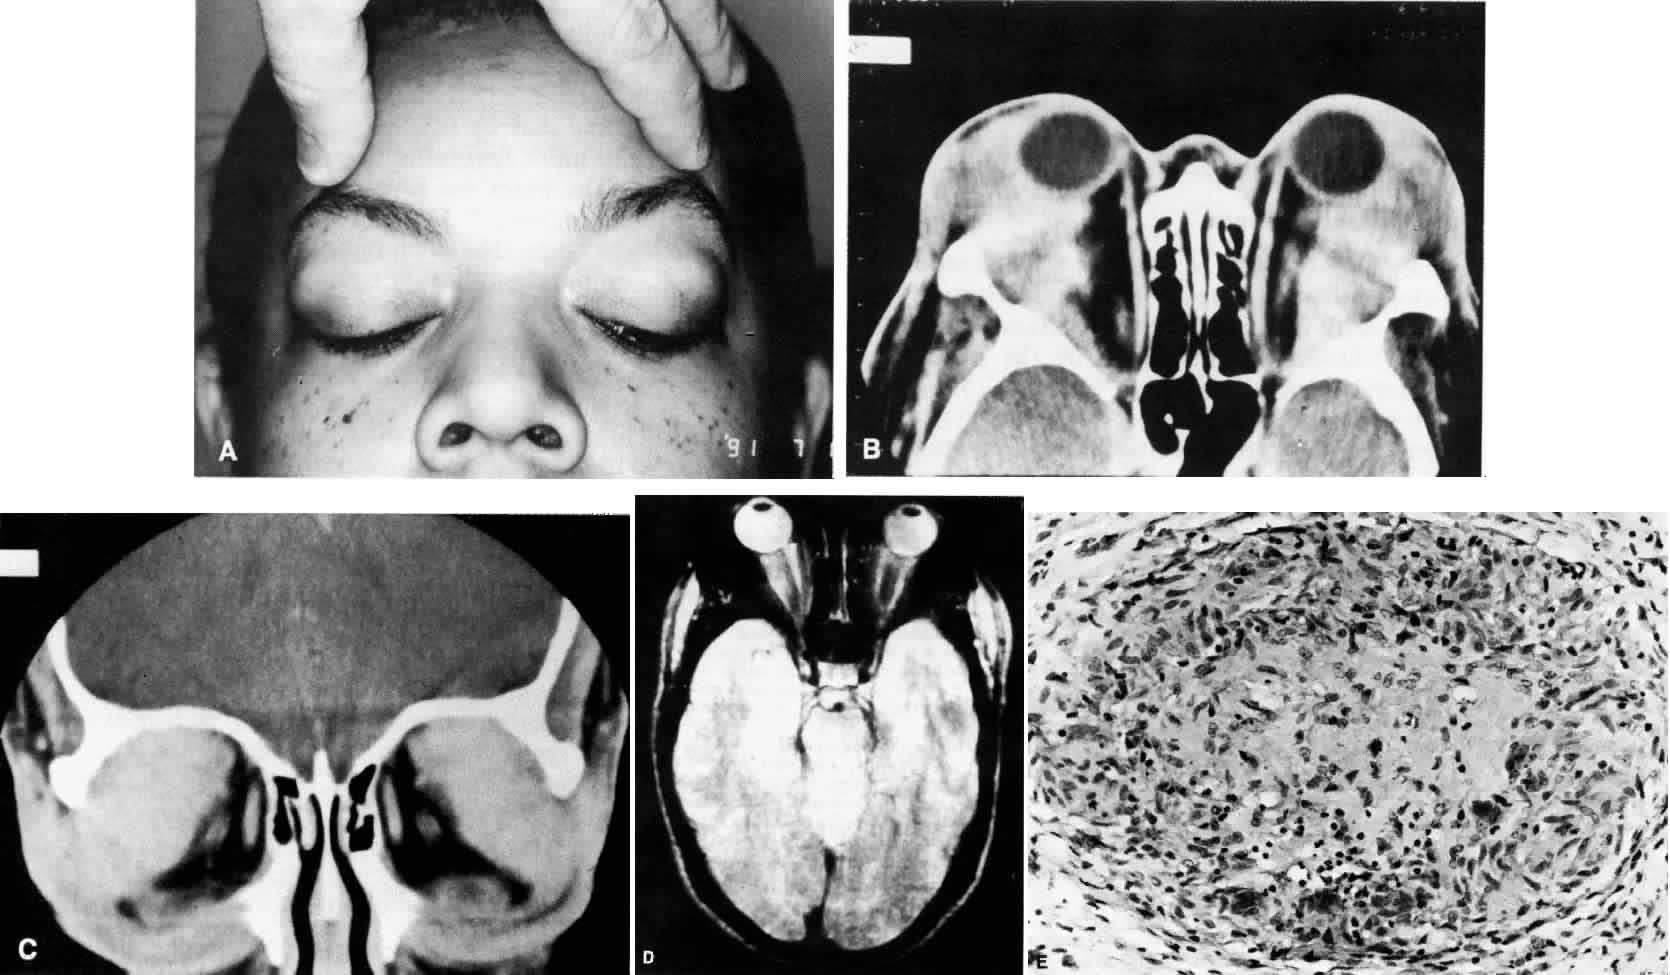

Differential Diagnosis

Diagnosis is established by biopsy of a symptomatic organ system. Lung, muscle, and skin are potential sites. The differential diagnosis includes classic polyarteritis nodosa, Wegener's granulomatosis, sarcoidosis, and aspergillosis. Unlike classic polyarteritis nodosa there is frequent involvement of the pulmonary vessels, with eosinophilic tissue infiltrates. The clinical findings of severe asthma and peripheral blood eosinophilia also help to distinguish the two entities.

Treatment

If untreated, the 5-year survival rate is 4%.217 Pulmonary, cardiac and renal lesions are common causes of death. With corticosteroid treatment, the 5-year survival rate improves to 50% to 60%. As in classic polyarteritic nodosa, chemotherapeutic agents can induce remission and have prevented relapse over a period of 10 years.208

TEMPORAL ARTERITIS

Temporal arteritis is well known to ophthalmologists because of its dramatic ocular presentation. It is a systemic disease that affects medium and large muscular arteries, primarily in the head, hence the alternate name cranial arteritis.218 The term giant cell arteritis is used by some authors to describe temporal arteritis, but Takayasu's arteritis, which occurs in young women and affects primarily the aortic arch, also is an arteritis with giant cells on histology and may properly be considered one of the giant cell arteritides.218 Takayasu's arteritis presents as transient, position-dependent visual loss and retinal changes that are caused by ischemia, but orbital disease is not a characteristic finding.

The incidence of temporal arteritis increases with age, with a dramatic increase in the very elderly.219 Even though more than 95% of cases occur in patients older than 50 years, age alone is not sufficient to rule out this diagnosis.218 Average age at onset of first symptoms is 70 years.218 There is a female predominance of 3:1.220

Systemic Manifestations

The systemic symptoms of temporal arteritis include headache or head tenderness, malaise, fatigue, fever, jaw claudication, polymyalgia rheumatica (characterized by proximal muscle weakness or pain), and arthralgias. Loss of the temporal artery pulse, tenderness over the artery, or an abnormality detected by palpation of the artery may occur, but the diagnosis should be considered even in the absence of these signs. Because many of the systemic symptoms are nonspecific, this diagnosis is often not considered until ocular symptoms are present.